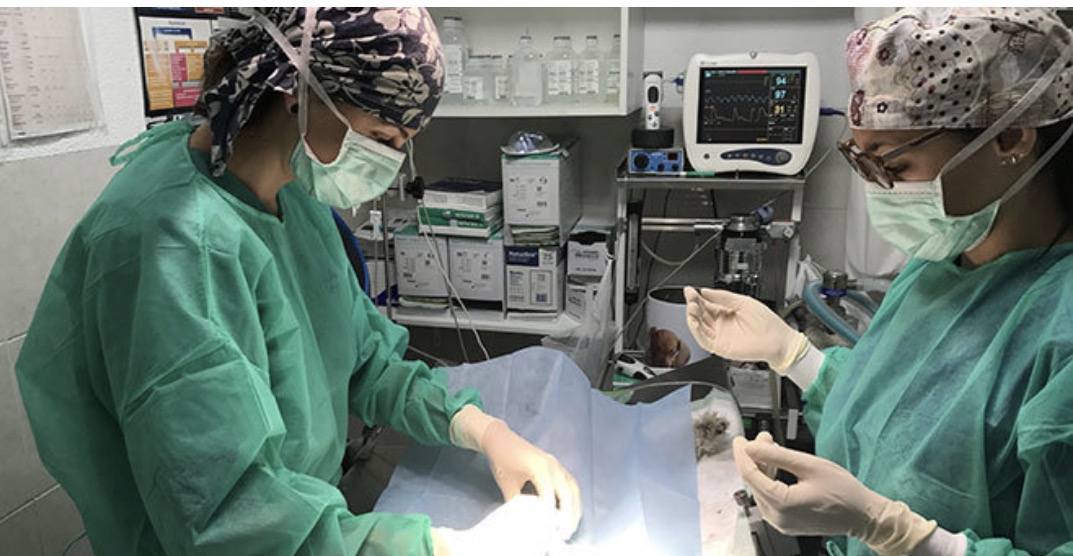

Centro Veterinario Los Ángeles-7Vidas, situado en Carrer Alvarado, 2, 03009 Alacant, Alicante, España, es un centro veterinario altamente valorado por su atención excepcional y profesionalismo. El centro cuenta con un equipo de veterinarios, incluyendo Oscar Beltrán, Yolanda, Fani, Marina, y Barbara, quienes se comprometen a garantizar la salud y bienestar de sus pacientes animales. El enfoque del centro se caracteriza por un alto nivel de atención al cliente, así como una profunda afectación y devoción hacia sus clientes, los animales. Clientes elogian repetidamente al centro por sus intervenciones impecables, el tratamiento excelente de mascotas y el enfoque cálido y humano de su personal.

Profesionales Experimentados

El equipo de profesionales experimentados del centro se compromete a proporcionar el nivel de atención más alto para cada paciente, asegurando su salud y felicidad.